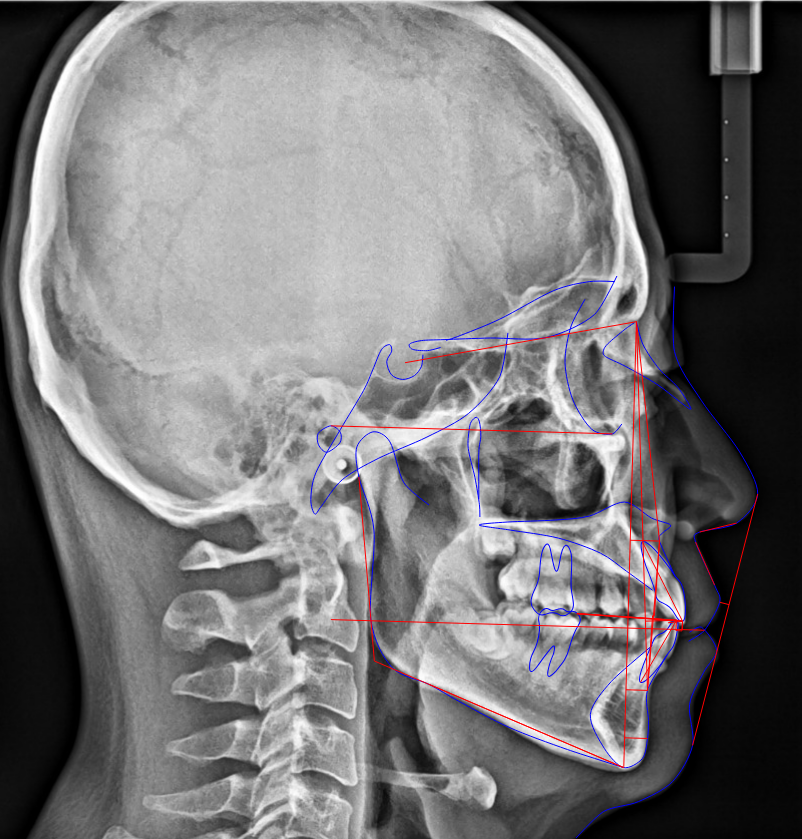

習慣の影響:指しゃぶり、舌で前歯を押す癖、口呼吸など。 当院では、セファロ分析を用いて「骨格の問題か、歯の生え方の問題か」を科学的に特定します。

当院では、全ての患者様に矯正歯科にしか置いてないセファロレントゲン(側貌頭部エックス線規格写真)という機械を使って分析を行っています。

「なんとなく下げる」のではなく、日本人の骨格黄金比と比較し、あなたの顔立ちにおいて「あと何ミリ下げるのが望ましいか」を、ミリ単位の数値で算出します。

- セファロで導くEライン:

鼻先と顎先を結んだラインに対し、唇がどこにあるのが理想か。数ミリ単位でシミュレーションします。 - 「下げすぎ」の防止: